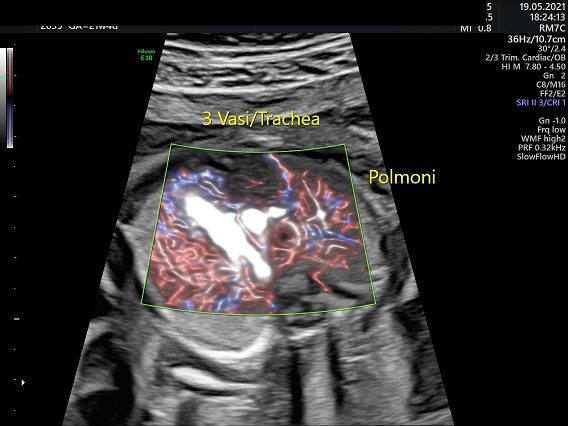

Torace:

Cuore fetale; dalla 20a settimana di gestazione con la scansione 4-camere, è possibile individuare il 40-50% delle cardiopatie. Alcune cardiopatie sono identificabili tuttavia solo attraverso la scansione dei tratti di efflusso ventricolari e cioè con la visione degli assi lunghi. Vi sono, inoltre, alcuni difetti cardiaci (piccoli difetti del setto ventricolare, difetti del setto atriale, anomalie del ritorno venoso polmonare, coartazione aortica, patologie valvolari) il cui riconoscimento ecografico è difficilissimo.

Riportiamo di seguito la sensibilità dell’ecografia eseguita entro la 24a settimana nel riconoscimento di alcuni difetti cardiaci: truncus arterioso 59%, trasposizione dei grossi vasi 21%, tetralogia di Fallot 49%, cuore univentricolare 45%, canale atrioventricolare 58%, anomalie della valvola polmonare 21%, anomalia di Ebstein 25%, stenosi aortica 12%, cuore sinistro ipoplasico 54%, coartazione dell’aorta 3,8%, difetto del setto ventricolare 11,5%, difetto del setto atriale 13,4%, stenosi/insufficienza mitralica 40%, situs inversus 55%.

Apparato respiratorio. La predittività ecografica delle anomalie dell’apparato respiratorio è del 3% (eurocat) per le anomalie delle vie respiratorie (laringe, trachea, bronchi); del 17% (eurocat) per la MAC (malattia adenomatoide Cistica); del 33% (eurocat) per la ipoplasia polmonare.